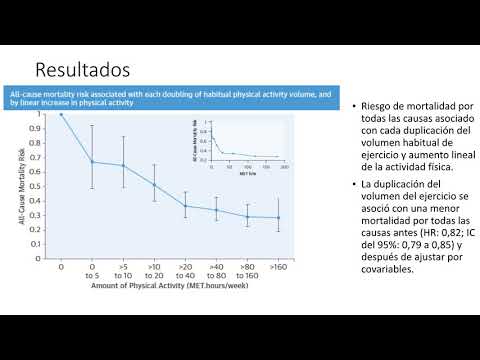

Actividad fisica y mortalidad en pacientes con enfermedad coronaria cronica. Dra. Carolina Pappalettere. Residencia de Cardiología. Hospital C. Argerich. Buenos Aires